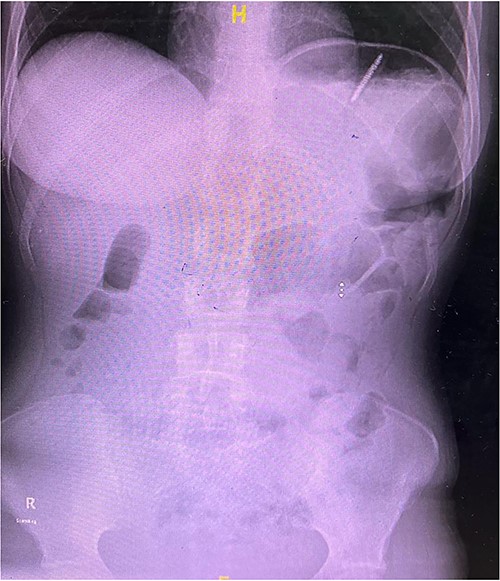

A 25-year-old female presented to the accident and emergency department with a history of accidentally ingested toothbrushes. The patient had a history of anorexia nervosa with multiple episodes of induced emesis. On presentation 3 hours post-ingestion, she was asymptomatic and vitally stable, with no physical abdominal findings. X-ray abdomen was ordered, which confirmed the presence of the toothbrush at the left upper quadrant (Fig. 1). The patient was counselled, and written consent was obtained for an upper oesophagogastroscopy extraction and possible surgery in case of failure of the initial procedure. The procedure was performed while the patient was under general anaesthesia, and the toothbrush was found at the fundus of the stomach (Fig. 2). It was extracted fully via a gastric balloon grasper by grasping the toothbrush from the head. A follow-up upper oesophagogastroscopy was conducted with no evidence of mucosal injury to the stomach or oesophagus. The procedure lasted for ~20 minutes. The patient was discharged after 6 hours and was referred to the psychiatry clinic for further assessment.

X-ray of abdomen showing the presence of a toothbrush at the left upper quadrant.